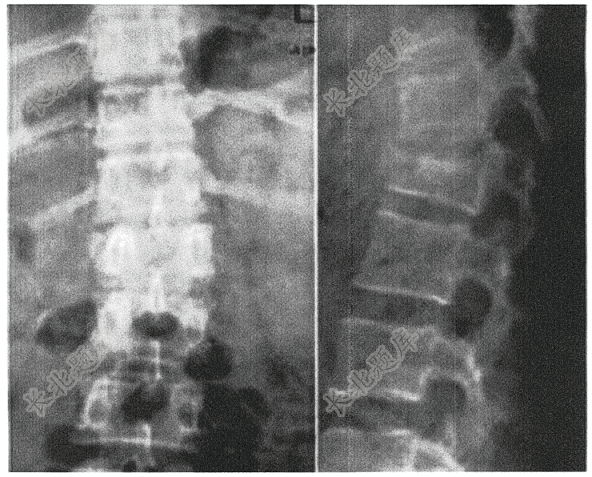

- 简答题患者女,35岁,外伤2小时。